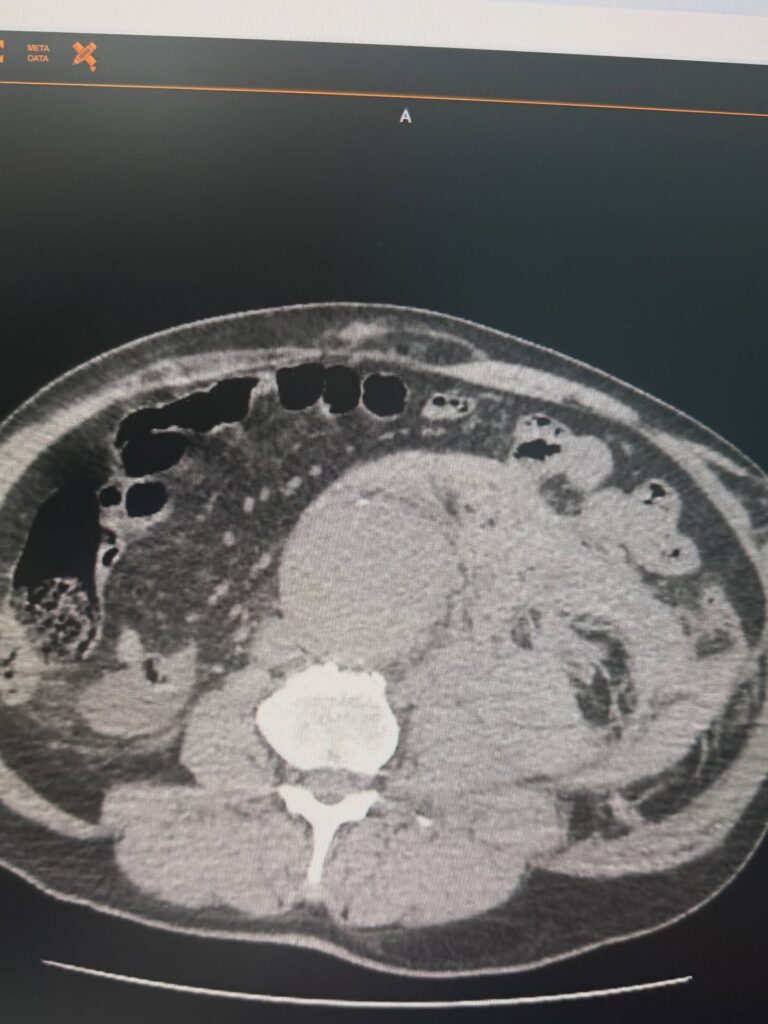

У Черкаській обласній лікарні успішно провели лікування пацієнта з розривом аневризми черевної аорти. Медики пояснюють, що це один з найнебезпечніших ургентних станів у судинній хірургії.

Медики зазначають, що в таких випадках рахунок іде на хвилини, а кожне рішення має критичне значення. Завдяки оперативній діагностиці, злагодженій роботі команди та своєчасному хірургічному втручанню вдалося врятувати життя пацієнта.